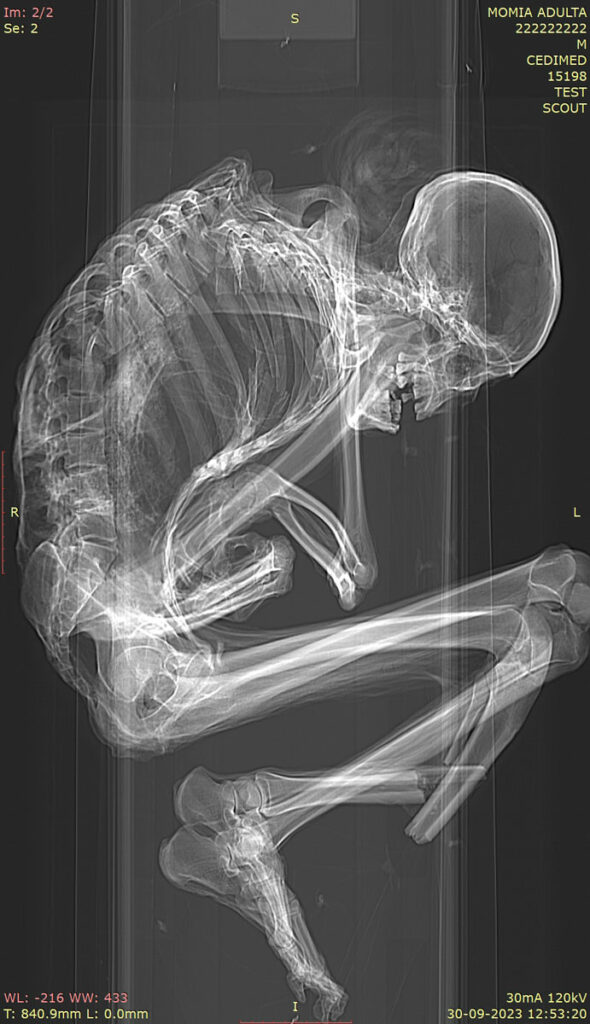

SANTIAGO, CHILE—Live Science reports that Catalina Morales and Francisco Garrido of Chile’s National Museum of Natural History examined the 1,100-year-old remains of a man unearthed in the Atacama Desert. At the time of the discovery in the 1970s, it was noted that the man’s lower left leg was broken, and that he had likely been involved in an accident in a nearby turquoise mine. The new study suggests that the man was between the ages of 25 and 40 at the time of death, sometime between A.D. 894 and 1016. X-rays and CT scans of the mummy show that he had suffered extensive trauma, likely caused by a rockfall or collapse in the mine. The injuries included fractures in the upper spine and displaced vertebrae; shoulder blade and collarbone fractures; and rib fractures and a collapsed rib cage. Such injuries are typically associated with severe spinal cord damage, the researchers explained. He was likely in a head-down position when the accident occurred, since there were no injuries found in his skull, neck, or arms. This suggests that he may have been mining—using a stone hammer to extract turquoise from the rock—or may have covered his head with his arms to protect himself from falling rocks. To read about the preservation of the region's mummified individuals, go to "Atacama's Decaying Mummies."